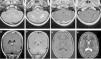

La histiocitosis de células de Langerhans (HCL) es una enfermedad rara caracterizada por la acumulación en los tejidos de células dendríticas anómalas similares a las células de Langerhans. La presentación clínica varía desde la aparición de una lesión ósea única hasta la afectación multisistémica. La implicación del sistema nervioso central (SNC), manifestada como diabetes insípida secundaria a afectación hipofisaria, es conocida desde la descripción original de la enfermedad. En la actualidad, se diferencian 2 tipos de lesiones del SNC: las lesiones seudotumorales, con infiltración por las células de Langerhans, cuya manifestación más frecuente es la infiltración hipofisaria, y otras, de más reciente descripción, las lesiones neurodegenerativas del SNC, asociadas a deterioro neurológico, que constituyen una complicación de la enfermedad de causa discutida. Nuestro objetivo es describir las manifestaciones radiológicas de la HCL en el SNC en los pacientes pediátricos.

Langerhans cell histiocytosis (LCH) is a rare disease characterized by the accumulation within tissues of anomalous dendritic cells similar to Langerhans cells. The clinical presentation varies, ranging from the appearance of a single bone lesion to multisystemic involvement. Central nervous system (CNS) involvement, manifesting as diabetes insipidus secondary to pituitary involvement, has been known since the original description of the disease. Two types of CNS lesions are currently differentiated. The first, pseudotumoral lesions with infiltration by Langerhans cells, most commonly manifests as pituitary infiltration. The second, described more recently, consists of neurodegenerative lesions of the CNS associated with neurologic deterioration. This second type of lesion constitutes a complication of the disease; however, there is no consensus about the cause of this complication. Our objective was to describe the radiologic manifestations of LCH in the CNS in pediatric patients.